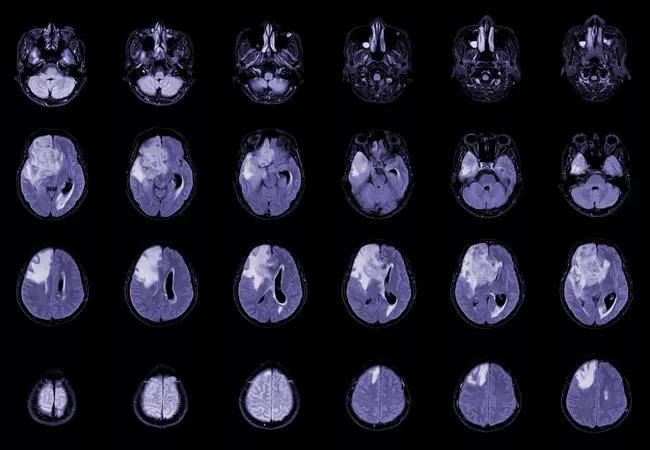

Pathway Cross-Talk Suggests New Approach to Glioblastoma Treatment

Cleveland Clinic Cancer Center researchers are honing in on how the currently-incurable primary brain tumor glioblastoma notoriously evades treatment, with their findings pointing to potential approaches that could stop the cancer in its tracks. The data was presented at the 2023 ASTRO annual meeting.

About 15,000 people per year in the United States are diagnosed with glioblastoma.